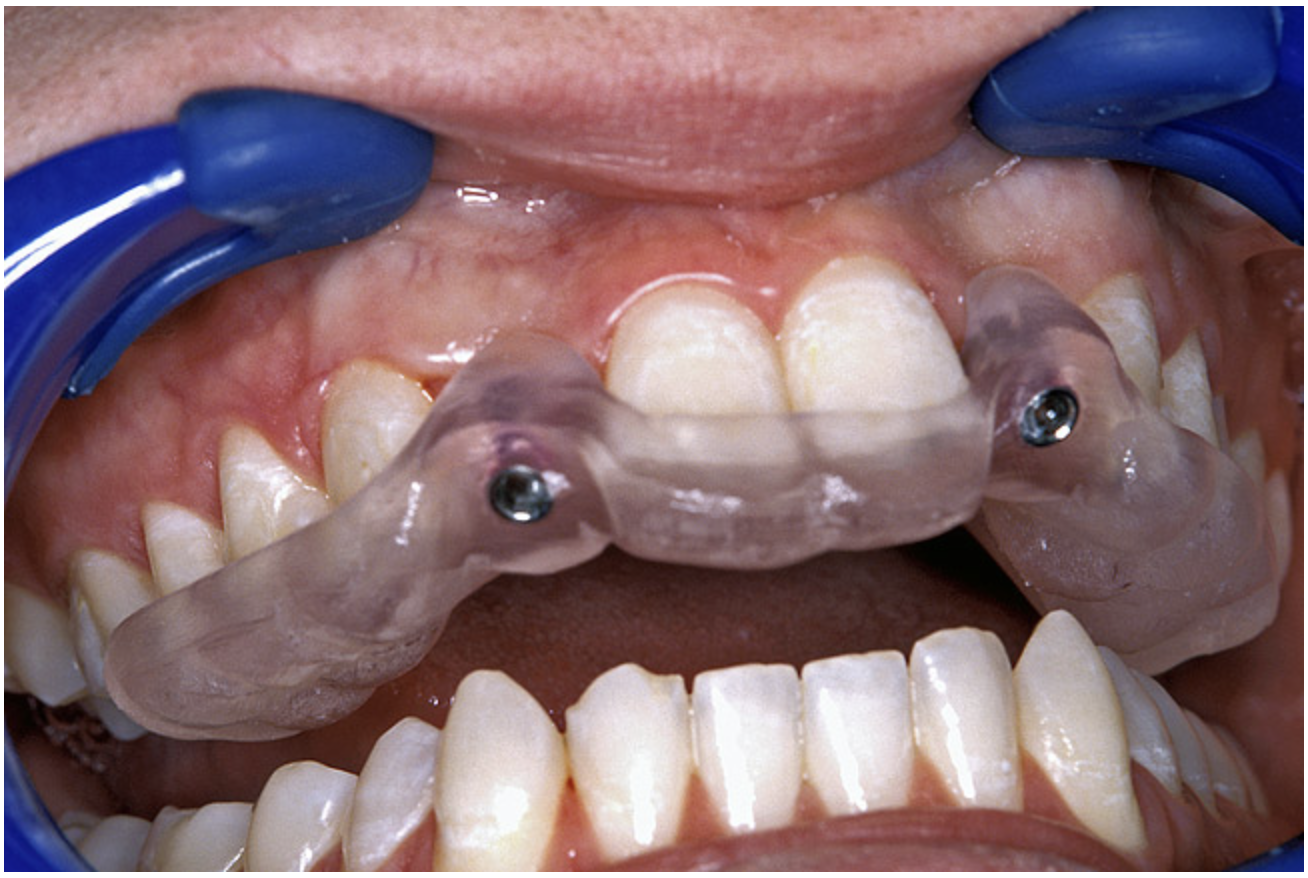

Periapical radiographs were taken to help determine the mesial-distal inclinations of the adjacent tooth roots (Figure 1). The radiographs revealed a serious issue, convergent roots for the right canine and right central, which eliminated that area as a potential implant-receptor site. The space between the left central and canine teeth was minimal, although the roots were relatively parallel. Clinical examination (manual palpation of the root eminences superiorly to the vestibule on the right side) confirmed the root convergence (Figure 2A). The flat, wide zone of the keratinized tissue and lack of interdental papilla was evident for the missing right lateral incisor. There was a marked difference in clinical appearance for the left lateral, which could impact the eventual plan of treatment (Figure 2B). Other significant clinical findings included bilateral facial bone concavities, which existed as a result of the congenitally missing tooth roots. As a diagnostic cue to the underlying bone topography, it is important to follow the demarcation between attached and unattached gingival tissue, and note the crestal width of the available keratinized tissue (Figure 2C).

Figure 1  Pretreatment radiographs revealed convergent roots for the right canine and right central.

Figure 1

Figure 2a  Pretreatment buccal views showed (A) root convergence, (B) a difference in clinical appearance of the left lateral, and (C) significant crestal width of keratinized tissue.

Figure 2a